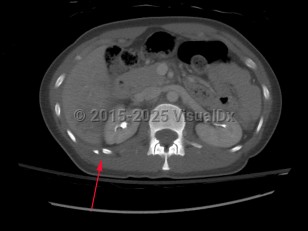

Causes / typical injury mechanism: Rib fractures are a common injury of the thoracic cage. They may be traumatic or pathologic. Depending on the location and the number of ribs involved, be alert for possible visceral injuries, pulmonary contusions, pneumothorax, or vascular injury.

Fractures of the lower ribs (9-12) could indicate concomitant intraabdominal injury.

Rib fractures are commonly described as:

- Rib number(s), right or left

- Acute or chronic with evidence of healing from a remote incident

- Nondisplaced, > 2 mm displacement, comminuted, or flail chest

- Presence or absence of visceral injury